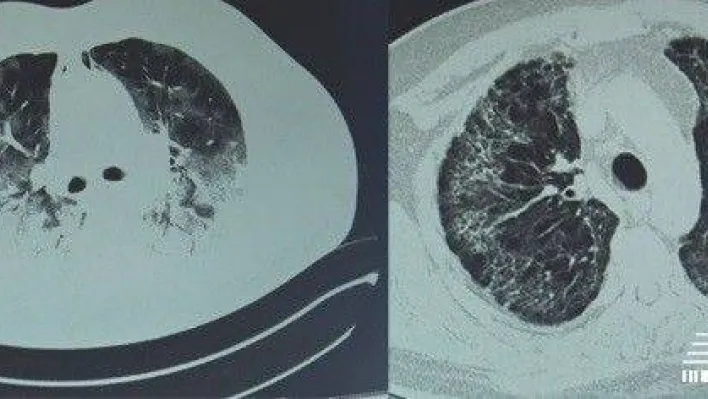

Koronavirüsün etkilediği kişilerden biri de İstanbul’da esnaflık yapan Ahmet Emecen oldu. Yüksek ateş ve öksürük şikayetiyle hastaneye giden Emecen’e koronavirüs testi yapıldı. Testin pozitif çıkması sonucu çekilen tomografide virüsün akciğerlerin yüzde 80’ini kapladığı belirlendi. Nefes almakta güçlük çeken Emecen, apar topar yoğun bakıma kaldırıldı. Koronavirüs tedavisine başlanan adam, tedaviye rağmen iyileşemedi. Doktorların ‘hastayı kurtaramıyoruz’ dediği bir dönemde Emecen son bir umutla İstinye Üniversite Hastanesi Medical Park Gaziosmanpaşa’ya sevk edildi. Emecen’e bu hastanede ozon tedavisi uygulandı.

"Yoğun bakım doktorumuz beni aradı. Tedaviye rağmen hastalığın ilerlediğini ve Ahmet beyi kurtaramadıklarını söyledi. Ne yapabiliriz diye düşündük. Ben klinik koronavirüs hastalarıma ozon terapi uyguluyordum. Sonuçların başarılı olduğunu, hastaların çabucak toparladığını gördüm. Ahmet beye de yoğun bakımda ozon terapi uygulamaya başladık. Tedaviye başladıktan sonra yaptığımız kontrollerde oksijen düzeylerinin kısa sürede yükseldiğini, nefes darlığının azaldığını görmeye başladık. Belli bir süre sonra yoğun bakımdan çıkarabileceğimizi yakınlarına söylediğimde kimse inanamadı. Ancak ozon tedavisi sonrası oksijen düzeyi klinikte tedavi edebileceğimiz düzeye geldi. Belli bir süre klinikte tedavi ettik. Klinikte yatarken de ozon tedavisi uyguladık ve her seferinde oksijeni gittikçe yükseldi. Bunun yanında vücut direnci ve beslenmesi de düzeldi." "OZON GÜÇLÜ BİR DEZENFEKTAN"

Ozon tedavisinin alerjisi olmayan herkese uygulanabileceğini anlatan Dr. Öğr. Üyesi Özdemir, "Ozon aynı zamanda kuvvetli bir dezenfektan. Hem bakteri hem de virüs üzerinde etkili. Uygun dozlarda kullanıldığında kandaki virüsleri parçalayacağını öngörmüştük. Koronavirüs kana saldıran bir virüs. Kandaki kırmızı hücrelere yerleşerek onları parçalayıp oradan besleniyor. Kana ozonu uyguladığımızda virüsün yok olduğunu ve belirtilerin gerilediğini tespit ettik. Koronavirüs hastalarında ozon tedavisini kullandık. Koronavirüs tedavisinde ozon terapisi ilk seçenek olarak kullanılabileceği gibi, diğer tedavilere destek olarak da tercih edilebilir."